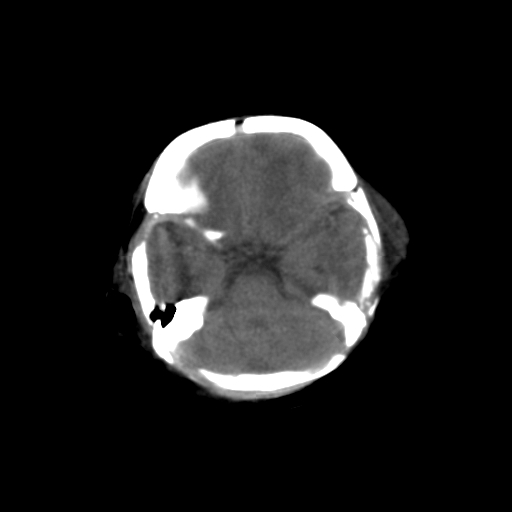

男,3天,患儿为剖腹产,生后嗜睡、拒乳。

1)考虑hie。2)sah?。3)右侧颞顶枕部及左侧颞顶部头皮血肿。

1、右侧颞顶枕部及左侧颞顶部头皮血肿。2、第五第六脑室。3、新生儿,脑白质密度还算可以,也无蛛血,不考虑hie。

脑室系统及脑沟裂闭塞,弥漫性脑密度减低,支持考虑hie,建议复查。右侧颞顶枕部及左侧颞顶部头皮血肿,另不除外胼胝体发育不良,复查